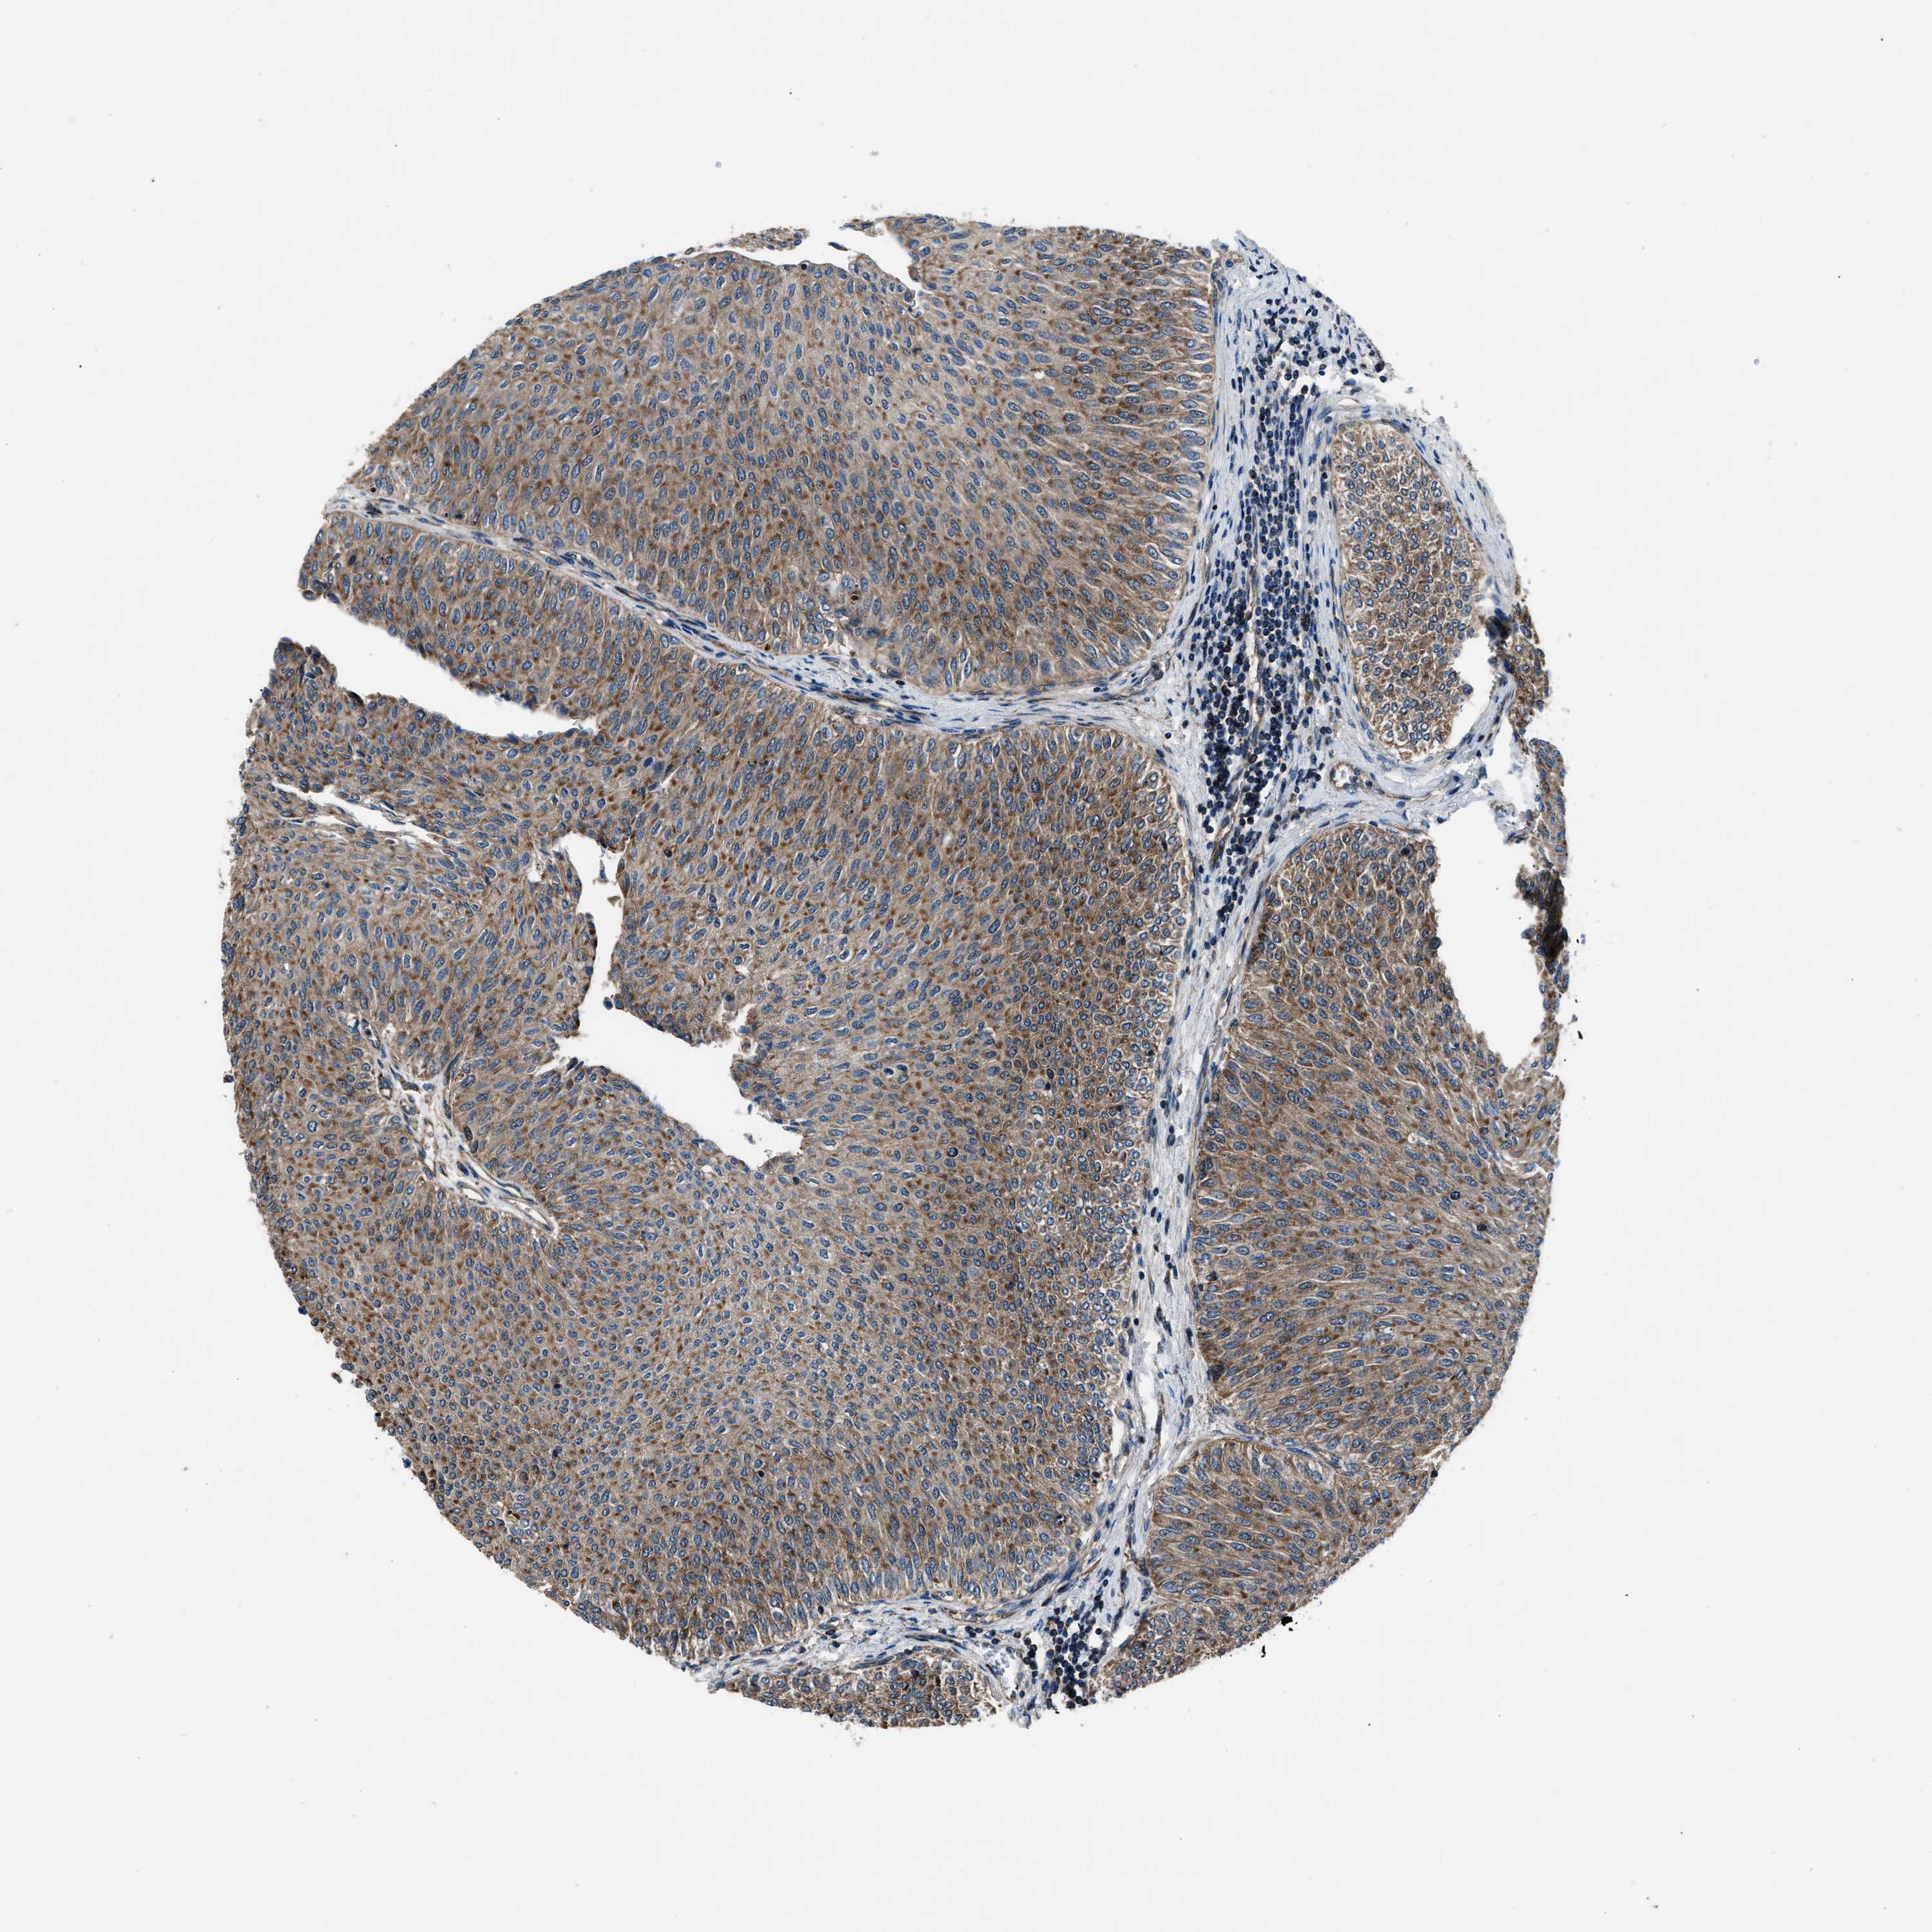

UROTHELIAL CANCER - Protein expressioni

A mouse-over function shows sample information and annotation data. Click on an image to view it in a full screen mode. Samples can be filtered based on level of antibody staining by selecting one or several of the following categories: high, medium, low and not detected. The assay and annotation is described here.

Note that samples used for immunohistochemistry by the Human Protein Atlas do not correspond to samples in the TCGA dataset.

Antibody stainingi

Antibody staining in the annotated cell types in the current human tissue is reported as not detected, low, medium, or high, based on conventional immunohistochemistry profiling in selected tissues. This score is based on the combination of the staining intensity and fraction of stained cells.

Each image is clickable and will lead to virtual microscopy that enables deeper exploration of all samples and also displays staining intensity scores, fraction scores and subcellular localization as well as patient and tissue information for each sample.

Antibody HPA020735

Staining

High

Medium

Low

Not detected

Intensity

Strong

Moderate

Weak

Negative

Quantity

>75%

75%-25%

<25%

None

Location

Urothelial carcinoma, Low grade

Urothelial carcinoma, High grade